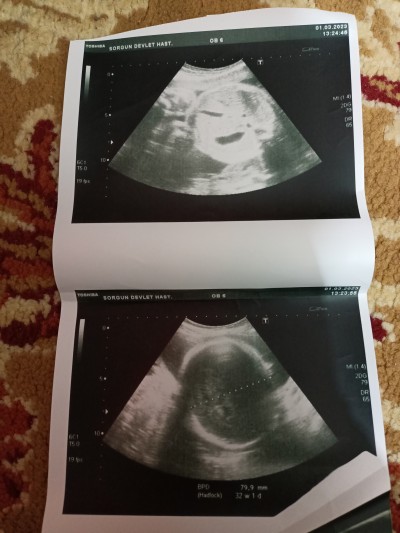

Acil bakar mısınız hadlock ne anlama geliyor

Hadlock nedir

Gebelik haftası

30

Normalmi sizce 79.9 mm olması